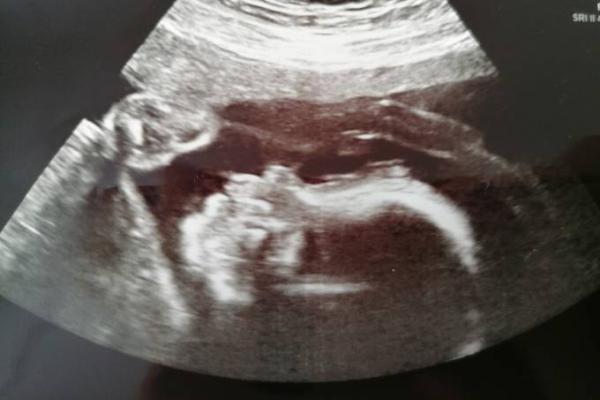

Hallo :) ich hatte heute meinen Zuckertest der zum Glück unauffällig war. Außerdem hat der kleine Mann seinen Zipfel so in den Ultraschall gehalten das es keine Zweifel mehr gibt und jeder Leihe das warscheinlich gesehen hätte :D Wird also wieder ein kleiner Junge Wir freuen uns sehr auf den kleinen Frosch, jetzt kannst shoppen losgehen :D die Sachen vom großen sind schon durchgeschaut.(der große ist aber ein Winter Baby) Ansonsten sah auch alles gut aus. Er hat jetzt ca. 600g und ist 28,5 cm groß :) Ein schönes Bild gab's auchnoch. Lg Hoff euch geht's allen gut :)

Oh ups stimmt. Da kommts.

Bild zu